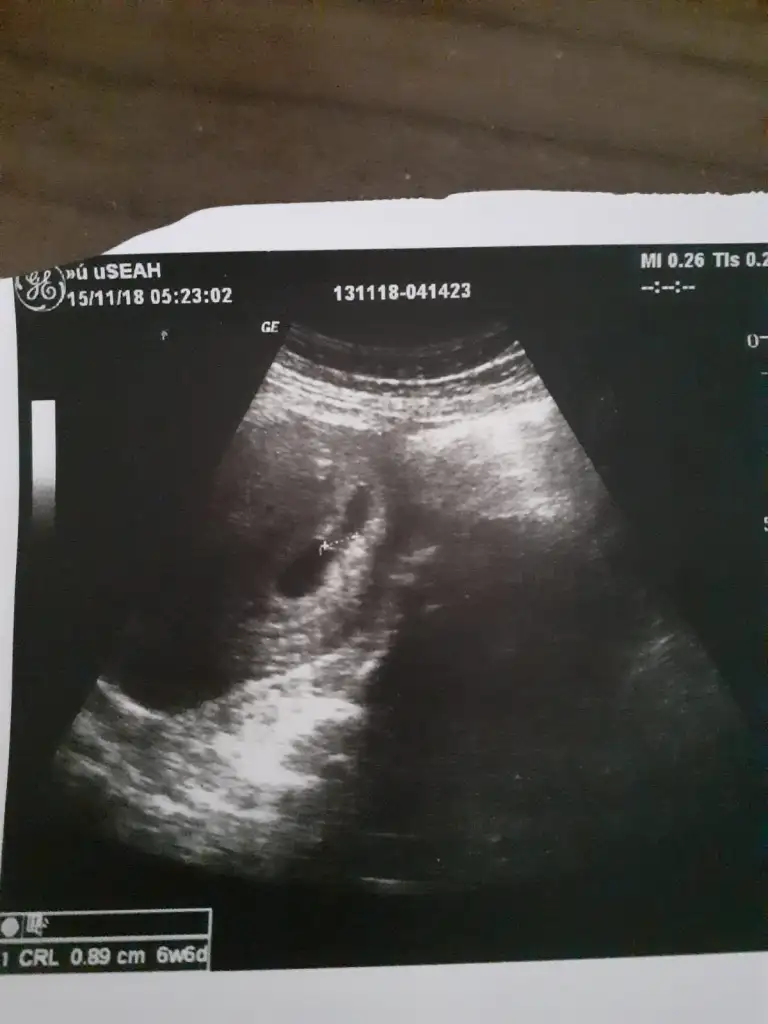

Erkek gibi geldi bana sizinkiKızlar 6+4 teki ultrason kağıdım kese bildiğin armut gibiydiYorumlayacak olan varmı?

Karından mı canımKizlar banada yorum yaparmisiniz rica etsem6+4 burda